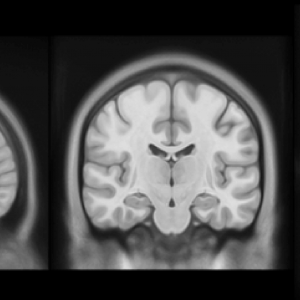

– Nowością jest fakt, iż badania były prowadzone w sposób podłużny, czyli każdy uczestnik badania był skanowany trzykrotnie – wyspany, po zarwanej nocy i po pięciu dniach niewystarczająco długiego snu, około pięciu godzin na dobę. Korzystaliśmy z rezonansu magnetycznego – przy jego użyciu skanowaliśmy mózg. Mogliśmy dzięki temu spojrzeć zarówno na jego anatomię, jak i funkcjonowanie. Do analizy tych danych wykorzystaliśmy teorię grafów, dzięki czemu udało nam się szczegółowo zmapować sieć połączeń funkcjonalnych w mózgu – tłumaczy Patrycja Ściślewska.

Wskutek niedoboru snu upośledzeniu ulegają funkcjonalne połączenia między obszarami mózgu. W szczególności wrażliwe są tzw. „huby” – obszary mózgu, które charakteryzują się największą liczbą połączeń. Mózg kompensuje sobie utratę połączeń, tworząc nowe drogi przepływu informacji. Wykorzystując uczenie maszynowe, naukowcy potrafią rozpoznać, czy dany obraz połączeń w mózgu należy do osoby chronicznie niewyspanej, czy do osoby, która zarwała noc.